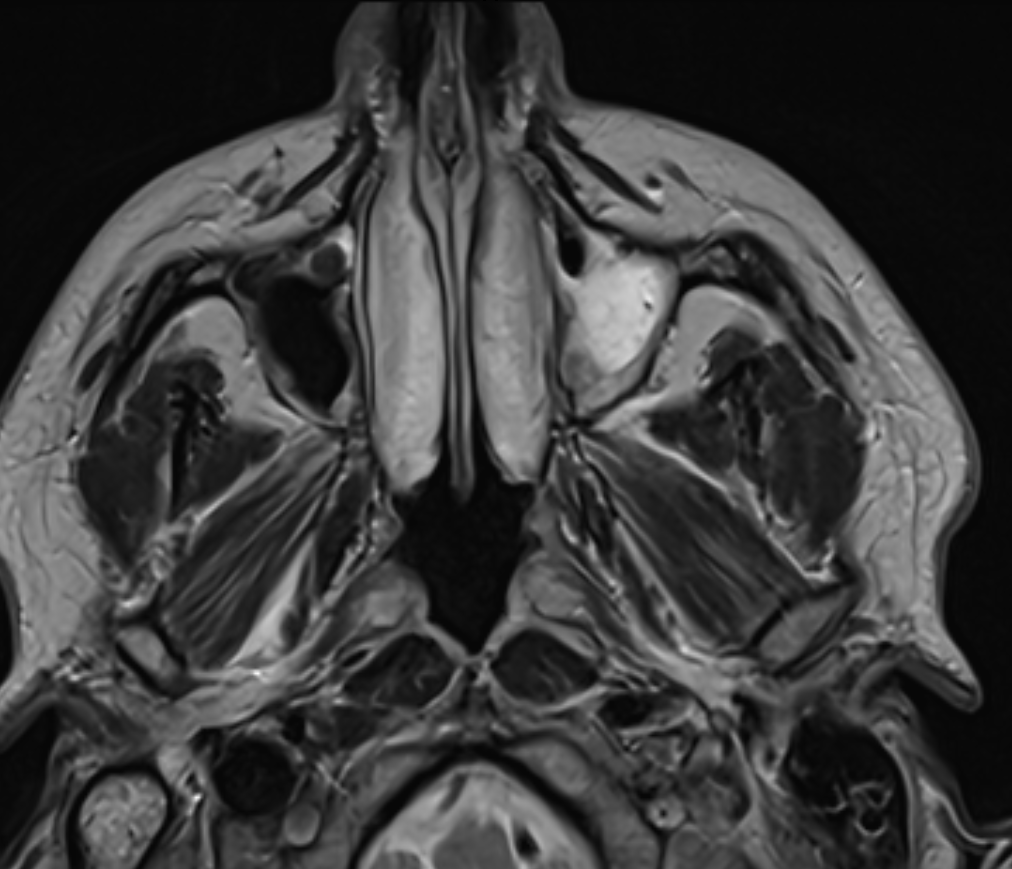

I have been experiencing constant tinnitus, head pain, inflammation & redness of my face for months now, relentlessly. Pain in my neck and spine, tingling, tremors, temperature deregulation, and muscle spasms on the left half of my body. I have had a million blood tests, multiple MRI's, and multiple CT scans, and they don't show anything conclusive despite the left side of my face being permanently red and yellow.

(The sinus cavity on the right here, my left, shows inflammation in bright white)